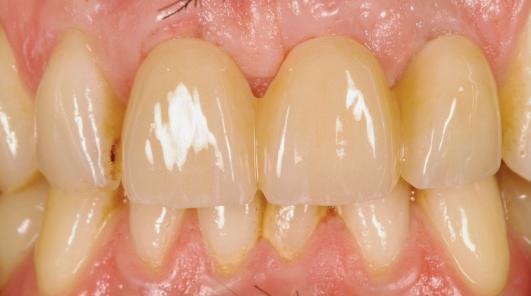

Adults could one day grow their own replacement teeth instead of having fillings – as scientists make a key discovery. This research offers a potential way to repair teeth and a natural dental treatment alternative.

While some animals like sharks and elephants can continuously grow new teeth, humans only have one set from adulthood. The ability to regenerate teeth would be a major leap forward for dentistry.

Unlike implants and fillings, which are fixed and cannot adapt over time, a labgrown tooth made from a patient’s own cells could integrate seamlessly into the jaw and repair itself like a natural tooth.

Xuechen Zhang, from the Faculty of Dentistry, Oral & Craniofacial Sciences, King’s College London, said: “Fillings aren’t the best solution for repairing teeth. Over time, they will weaken tooth structure, have a limited lifespan, and can lead to further decay or sensitivity. Implants require invasive surgery and good combination of implants and alveolar bone. Both solutions are artificial and don’t fully restore natural tooth function, potentially leading to long-term complications.”

“Lab-grown teeth would naturally regenerate, integrating into the jaw as

real teeth. They would be stronger, longer lasting, and free from rejection risks, offering a more durable and biologically compatible solution than fillings or implants.”